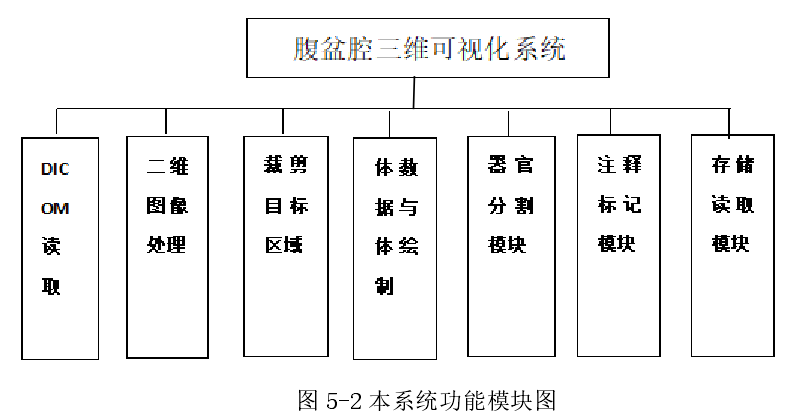

第五章 医学图像三维可视化系统搭建

5.3 图像数据控制部分

5.3.1 医学图像输入输出

ITK工具包里的ImageIOBase类里封装了所有医学图像数据的读写方法,系统对于医学图像的访问就依赖于这个类。在应用过程中系统通常需要读取的是一个图像序列,比如上文提到的DICOM格式的文件,这时利用ITK提供的itkSeriesReader来进行读取。

5.3.2 系统图像格式

将医学图像文件读入内存之后,为了方便系统对图像数据进行操作,需要将这些格式统一转换为系统内部的图像格式。比如在本系统中定义了两种图像的抽象类SImage和SPolygonal,分别用来构造图像类别(DICOM 文件格式)和多边形类别(vtk文件格式)。 其中 SImage 类里包含图像数据灰度值矩阵 S_data,图像名称 S_name,图像路径 S_path,图像原点 S_origin,图像读写锁 S_RWlock 等。而 SPolygonal 相对较为简单一些有图像名称P_name,图像路径 P_path,P_PolyData 此成员是 vtkPolyData 类型的。

5.3.3 图像数据item的树形结构

为了实现图像可视化的需求,上文中写到的图像数据结构需要加入一些新的属性(图像绘制器种类、绘制参数等等)进行封装形成一个数据节点用 dataNode 表示。之后需要建立一个树形结构 dataTree 来存储和管理所有的数据节点。在 dataTree 内定义了数据节点的增删改获取等接口,每个数据节点包含了图像数据(灰度值矩阵)和图像属性两部分构成。系统中不能直接对图像数据进行访问需要通过树结构 dataTree,这大大增加了数据的安全性。

5.3.4 用户图形界面UI设计

5.4 图像模型显示部分

显示模块是用来把图像信息显示给用户的模块,本系统中用户界面上有 4 个基础视图,分别是医学图像的 3 个轴位面横断面、冠状面、矢状面视图,还有一个是模型视图用来显示三维模型。